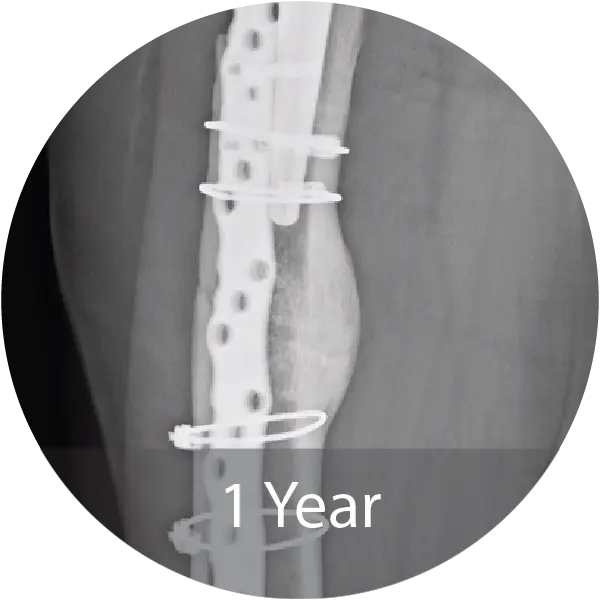

Case of an 81-year-old female with a periprosthetic femoral non-unionfracture and failed hardware treated with repeat ORIF and NMP fibers hydrated with saline. Progressive callus formation on x-ray and patient reported no pain and full range of motion 1 year post-op.